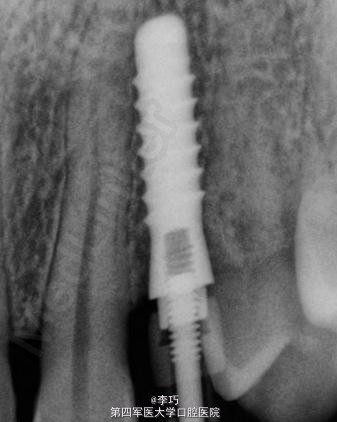

曲面体层片显示乳牙滞留

拔除滞留乳牙后进行种植治疗